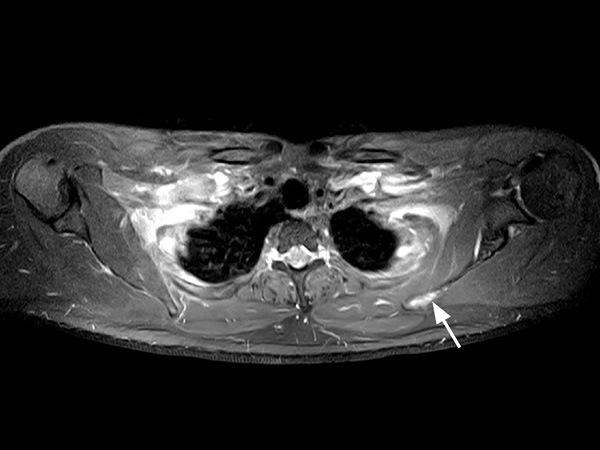

A 33-year-old male with history of non-Hodgkin lymphoma undergoes an MRI exam on Ingenia 1.5T to visualize clinically suspected recurrent disease. Whole-Body MRI was performed using T1W TSE and STIR imaging (4 stations, matrix 400x400, 6 mm slices). Additional whole-body diffusion imaging (3 stations, matrix 192x192, 6 mm slices) with MIP unmasks a focal area of diffusion restriction in the left scapular region. Subsequent contrast-enhanced 3D mDIXON imaging reveals a bone manifestation of a lesion in the left scapular angle. Furthermore, multifocal splenic infiltration is depicted. Note that the splenic lesions are veiled by the high physiological background diffusion signal in splenic tissue. The findings are compatible with skeletal and splenic tumor recurrence of non-Hodgkin lymphoma. Further total body follow-up imaging according to therapeutic regime is advised. Whole-body MRI allows rapid visualization of lesions in this lymphoma patient. A finding of multifocal organ manifestations has a decisive impact on further patient management and therapeutic regime. The fully digital Ingenia 1.5T MR system allows for rapid whole-body MRI with homogenously high imaging quality in depicting these lesions. Additionally, state-of-the art techniques such as whole body DWI can be included in the exam protocol, which further enhances the capability for visualizing lesions in oncology patients.

T1w mDIXON-FFE